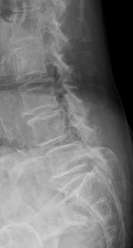

階段状に腰椎が変性すべりをおこしている症例

【術前】

第2, 第3, 第4腰椎に前方への変性すべりを認めます。痛みのため背中を反って立てないことが分かります。MRIではいずれの椎間でも強い脊柱管狭窄が発生し、神経が圧迫されているのが分かります。